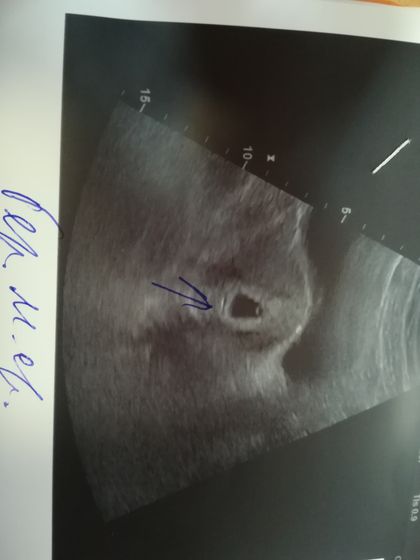

Когда только узнала что беременна сделала цифровой тест, он показал 2-3 недели(ниже есть тест). Через две недели сделала повторный тест, яркие две полоски. Через 3 дня сделала узи, сказали беременность малого срока, примерно 4 недели. Какой срок в итоге понять не могу. По месячным срок 6 недель, последние были 1 ноября, цикл не регулярный.